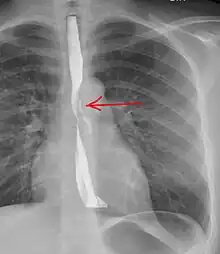

Upright chest radiography showing mediastinal air adjacent to the aorta and tracking cephalad adjacent to the left common carotid artery. This patient presented to the Emergency department with severe chest pain after eating. -